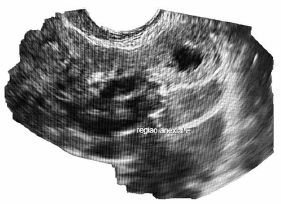

C.V.R.S., 36 anos, G VII P VI (6N) A0, IG cr: 6 semanas,deu entrada no PSGO com sangramento vaginal há cerca de 1 semana. Sem ultrassom prévio. Ao exame físico: especular: colo uterino sem lesões, mínima quantidade de sangue vermelho escuro em fórnice posterior. TV (toque vaginal) bimanual: colo impérvio, grosso, posterior. Ausência de dor à mobilização do colo uterino. Abdome: DB negativo, dor leve à palpação profunda de hipogástrio. Submetida à ultrassonografia transvaginal (imagens a seguir: figuras 1, 2, 3, 4) e beta HCG quantitativo: 9 000 UI/mL. Resultado de beta HCG 24h antes: 7 000 UI/mL.

Figura 1 (útero; EE 5 mm)